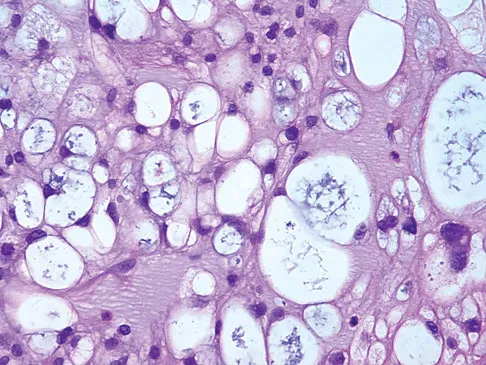

The biopsy specimens seen in Figures 55a and 55b are from a lytic lesion in the sacrum of a 58-year-old man. What is the most likely diagnosis?

Explanation

The lesion is a chordoma and the other listed choices can be eliminated based on the histology. Many tumors can occur in the sacrum including chordoma, multiple myeloma, giant cell tumor, aneurysmal bone cyst, and metastatic disease. The histology in this patient shows a lobulated lesion on low power with fibrous septae separating the lobules. At higher magnification, the cells have eosinophilic vacuolated cytoplasm and are called physaliferous cells. Chordoma is a low-grade neoplasm that most commonly occurs in the sacrum and rarely in the base of the skull. The diagnosis is often delayed. Chordoma is thought to originate from notochordal remnants. Chordoma typically occurs in the midline and has an associated soft-tissue mass. Wold LE, Adler CP, Sim FH, et al: Atlas of Orthopedic Pathology, ed 2. Philadelphia, PA, WB Saunders, 2003, p 372. Fuchs B, Dickey ID, Yaszemski MJ, et al: Operative management of sacral chordoma. J Bone Joint Surg Am 2005;87:2211-2216.